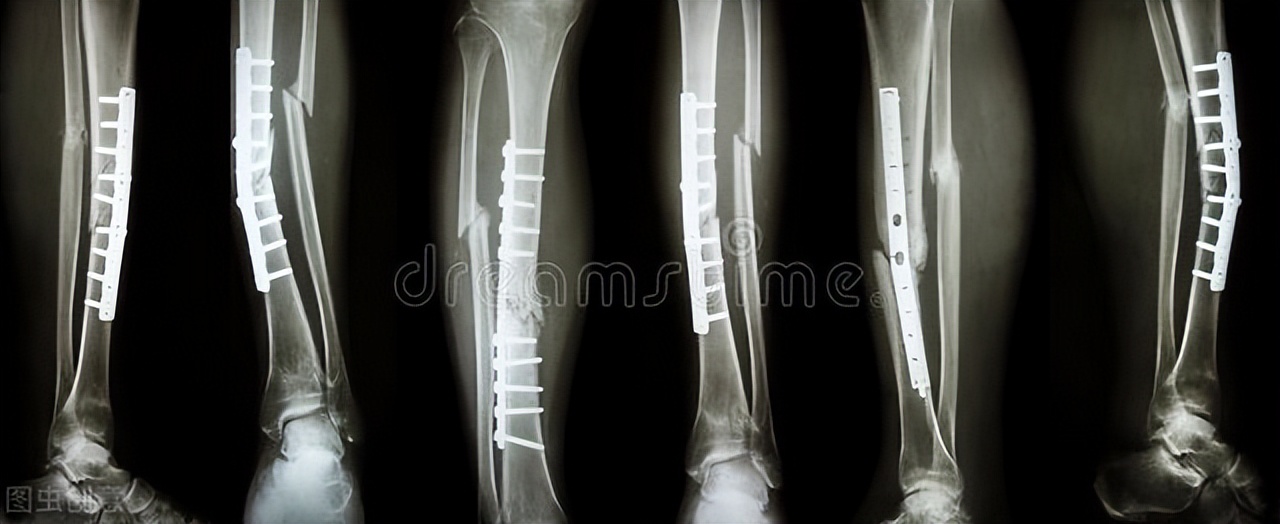

最常见的就是 钢板, 比如胳膊骨折了,都可以考虑运用钢板固定。

当然除了骨折之外,一些其他骨科疾病可能也需要用到金属内固定物,比如:腰椎和颈椎的相关疾病,也可能需要用到金属固定物。